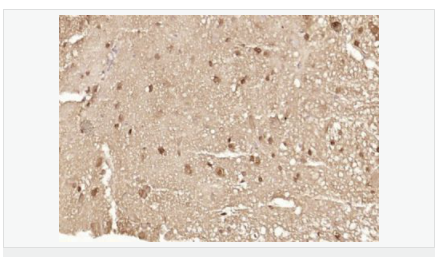

細(xì)胞定位細(xì)胞核 細(xì)胞漿

產(chǎn)品介紹The human ataxin-7 gene, also known as spinocerebellar ataxia 7 or SCA7, maps to chromosome 3p13-p12, has a 2,727-bp open reading frame, and encodes a 892 amino acid protein containing a nuclear localization signal and a polyglutamine tract (1,2). SCA7 is an autosomal dominant neurodegenerative disorder characterized by ataxia and selective neuronal cell loss caused by the expansion of a translated CAG repeat encoding a polyglutamine tract in ataxin-7, which is the SCA7 gene product (3,4). Ataxin-7 is expressed within neurons both affected and unaffected in SCA7 pathology with subcellular localization being variable depending upon the neuronal subtype (5). Polyglutamine expanded in ataxin-7 may carry out its pathogenic effects in the nucleus by altering the matrix-associated nuclear structure and/or by disrupting nucleolar function (6).

Ataxin 7 is a protein of unknown function. It may be the human orthologue of the yeast SAGA SGF73 subunit and a subunit of the human TFTC-like transcriptional complexes. Spinocerebellar ataxia 7 (one of a group of hereditary neurodegenrative diseases) is caused by an expanded trinucleotide repeat in the gene encoding ataxin 7. Ataxin 7 is typically located in the cytoplasm and on the nuclear membrane of normal brain neurons. In cells where there is a mutation of the SCA7 gene, ataxin 7 accumulates in intranuclear inclusions and can result in cell death.